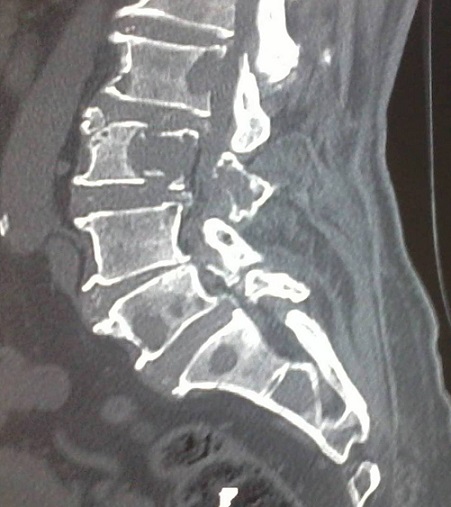

Le myélome multiple à Ig D est une entité rare (1 à 3 % des myélomes multiples), caractérisée par sa sévérité clinique et son mauvais pronostic. Le sous-type à Ig D Kappa n'en représente que 10 à 30 %. Nous rapportons l'observation d'un patient âgé de 70 ans, sans antécédents pathologiques, hospitalisé pour des lombosciatiques L3 bilatérales, hyperalgiques, d'allure inflammatoire et rebelles aux antalgiques usuels, associées à une altération de l'état général. L'examen trouvait un patient en mauvais état général, apyrétique et une pâleur cutanéo-muqueuse. L'examen neurologique était normal. Il n'y avait pas d'hépatomégalie ni de splénomégalie ni d'adénopathie palpable. Le bilan biologique montrait une vitesse de sédimentation à 90 mm à la première heure, une protéine C-réactive à 12 mg/L et une anémie normochrome normocytaire arégénerative à 8 g/dl d'hémoglobuline. L'électrophorèse des protéines a montré une hypoalbuminémie à 24 g/l, une hypergammaglobulinémie sans pic monoclonal. L'immunoélectrophorèse a montré une discrète bande gamma à Ig D Kappa dans le sang et une bande homogène Kappa liée et libre dans les urines. Il n'y avait pas de protéinurie de Bence- Jones. La calcémie corrigée était à 3 mmol/l. La créatinémie était à 183 μmol/l. Le myélogramme montrait une plasmocytose médullaire à 35 % faite de plasmocytes dystrophiques. La recherche d'amylose par biopsie des glandes salivaires accessoires était négative. Les radiographies du rachis lombaire montraient des signes des lésions ostéolytiques avec tassements vertébraux. La tomodensitométrie du rachis montrait une atteinte osseuse lytique multifocale intéressant la totalité des vertèbres lombaires mais touchant son maximum au niveau de L3, où elle s'accompagnait d'une épidurite. Une polychimiothérapie associée aux biphosphonates était instaurée avec amélioration des douleurs lombaires et de l'insuffisance rénale.